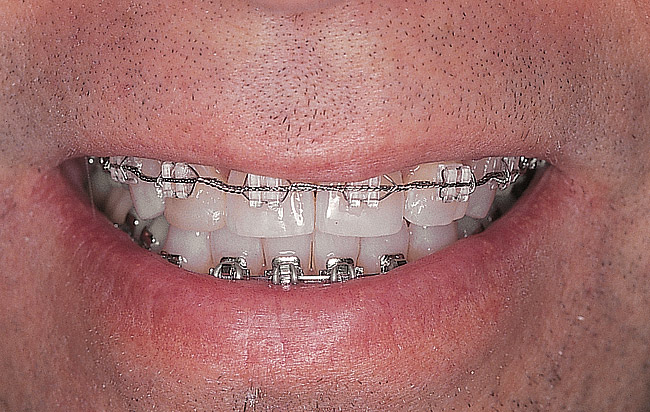

Figure 3  Preoperative intraoral facial view.

Figure 3